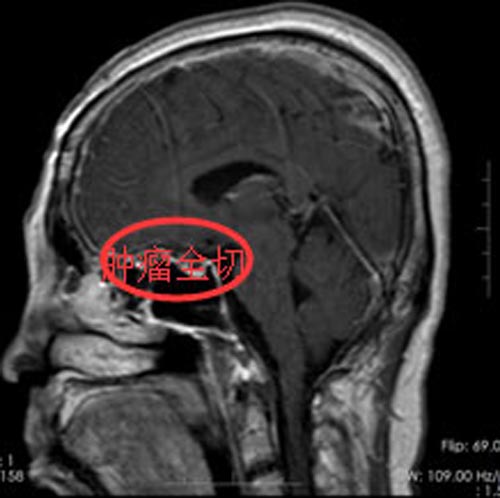

近2个月病情有加重趋势,并伴有头痛症状,当地医院行CT检查,结果示:鞍区占位。广东三九脑科医院头颅MR提示:1.鞍区巨大型占位性病变,肿瘤大小约2.1cm×1.9cm×1.1cm。2.梗阻性脑积水。陈姐及家人都同意手术治疗,由综合神经外科科鲁明副院长主刀行“鞍区巨大型占位性病变切除术”,手术顺利,术后病理示:鞍区脑膜瘤。术后经过一段时间的抗感染、脱水、营养神经、对症支持治疗后,陈姐恢复很好,视力较术前好转,重影症状消失。

▲手术后